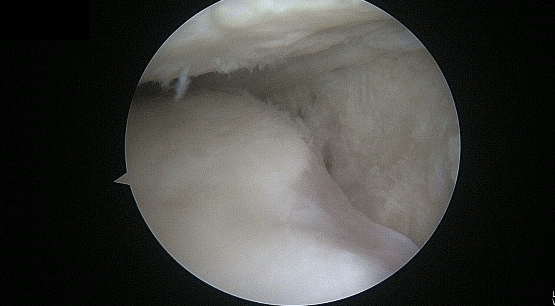

무릎관절경수술은 무릎을 절개하지 않고 5mm정도의 2-3개구멍을 뚫어 관절경을 이용하여 시행 하는 수술로 무릎연골판 수술 및 십자인대재건술, 연골 미세천공술에 주로 시행하는 수술방법입니다.

반월상연골판이 파열되면 무릎에서 끼는 현상 즉 잠김 현상이 발생하여 무릎을 굽힌 상태에서 잘 펴지 못하거나 펴진 상태에서 잘 구부리지 못하는 증상이 생깁니다. 이는 파열된 연골판이 대퇴골 연골과 경골 연골 사이에 끼여 발생되는 증상으로 이 상태를 방치하면 파열된 연골판이 점점 더 파열되어 치료가 더 어려워 집니다. 따라서 이 경우 MRI검사를 통해 정확한 진단을 시행한 후 그에 맞는 치료를 시행하여야 합니다.

<파열된 반월상연골판>

<부분절제술 시행 후 정리된 반월상연골판>

<봉합술 시행 후 정리된 연골판>